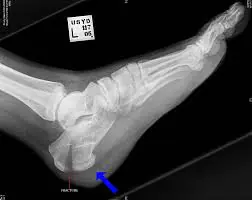

Il ginocchio varo è solitamente associato a un piede cavo.

Il medico potrebbe richiedere anche test di imaging, quali raggi X e risonanza magnetica del ginocchio. Un importante varismo del ginocchio, infatti, potrebbe dipendere da un’eccessiva usura delle cartilagini articolari, come nel caso di artrosi avanzate.